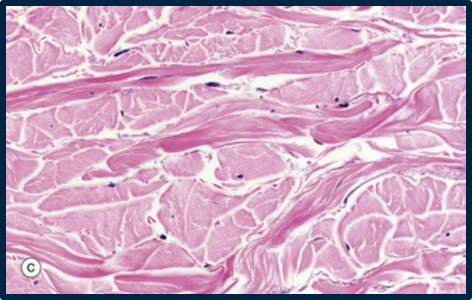

cardiac muscle